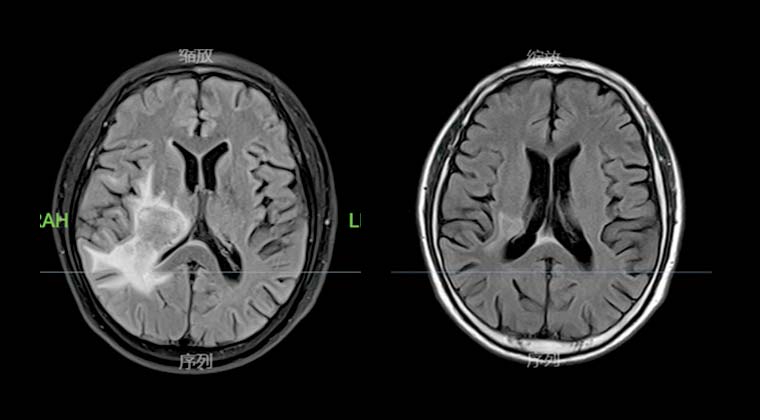

② Случай 2:

Пациент: мужчина, 67 лет

Вторичная злокачественная опухоль мозга

Лечение с помощью Киберножа начато 002020, назначенная доза составила 95% GTV DT15Gy, выполненная в 3 сеанса по 5Gy каждая.

Через 3 месяца после лечения повторная визуализация показала значительное уменьшение опухоли по сравнению с предыдущими обследованиями.

До лечения: После лечения: